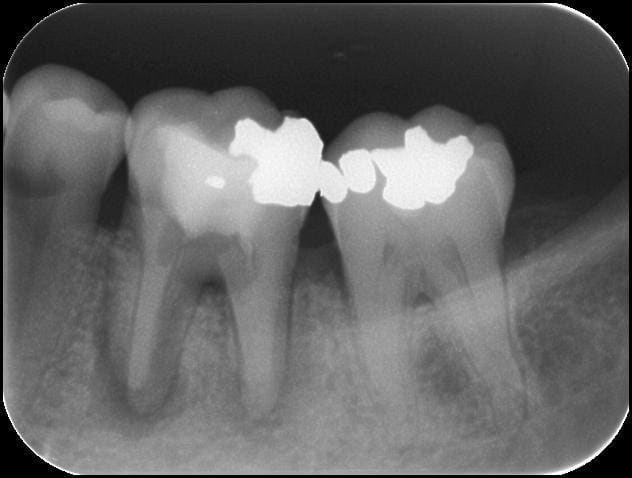

cf radio jour J

46 caoh2 i7ujgk - Eugenol